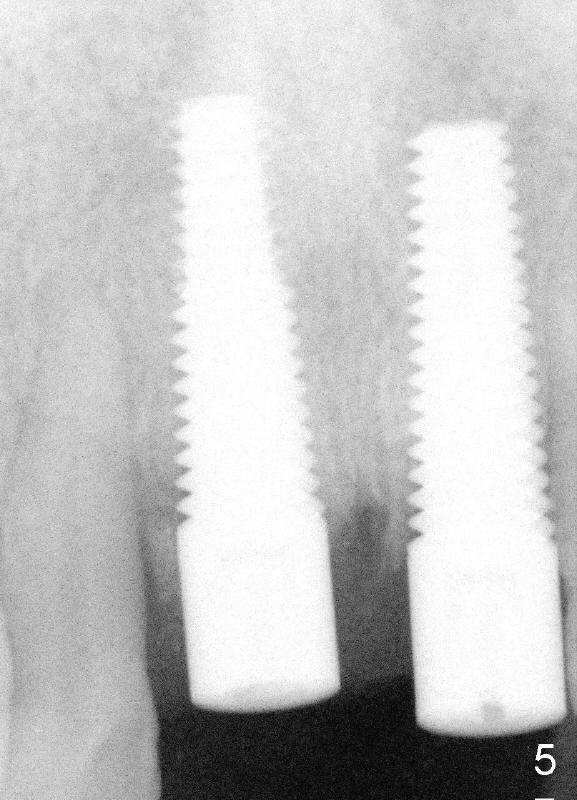

An immediate implant is planned for #9.  Bicon reamers are being used to harvest autogeneous bone from #9 socket during osteotomy (Fig.2). 5x20 mm Tatum tapered implant is inserted with primary stability (Fig.3).  The socket of #8 is debrided, irrigated with copious normal saline and Tetracycline solution, grafted with autogenous bone and Pure Phase Beta-Tricalcium Phosphate and covered by Resorbable Collagen Membrane.

Wounds heal uneventfully. Two months later, an implant is placed at the site of #8 (Fig.5).  Fig.4 is a preop X-ray, showing graft (*).  Two weeks later, swelling and pain recur (Fig.7).  Amoxicillin 500 mg tid is prescribed for a week.  Symptoms and signs improve after antibiotic treatment (Fig.8).  A month later, the patient complains tenderness on touching the implant of #8 without swelling.  A X-ray film is taken (Fig.6).  The symptom is again controlled while taking oral Clindamycin and relapses when treatment is terminated.  What should we do?